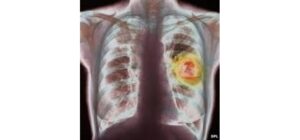

Tổng quan về ung thư phế quản

Tổng quan về ung thư phế quản UNG THƯ PHỔI TS.BS. Lê Khắc Bảo – Giảng viên Đại học Y Dược TPHCM Phó khoa hô hấp Bệnh Viện Nhân Dân Gia Định Cố vấn Trung tâm điều trị bệnh hô hấp Phổi Việt     TÓM TẮT Ung thư phế quản (thường gọi là ung thư […]